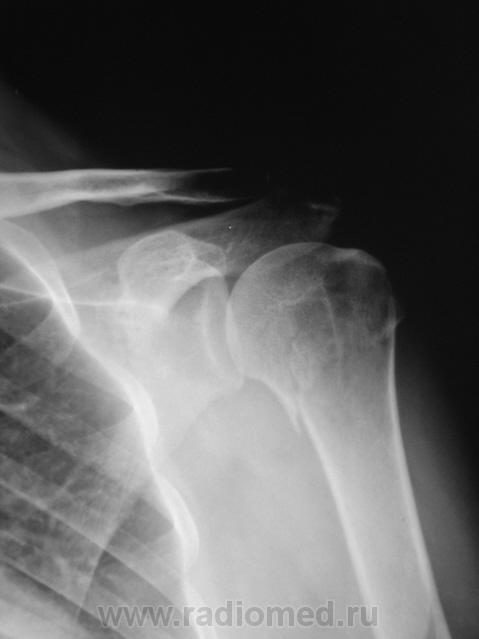

Травма. Пациент направлен на рентгенографию плечевого сустава.

хирургической шейки, вколоченный, с отрывом большого бугра.

Всего бугорка?